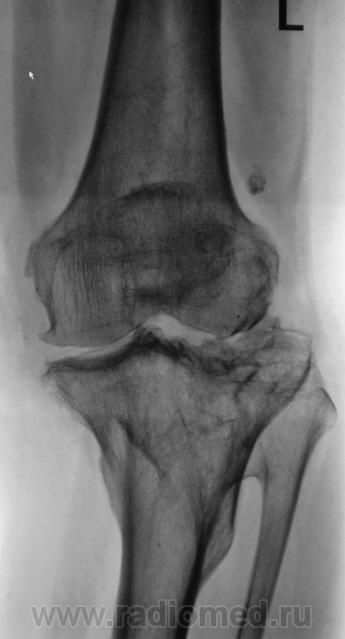

Пациентка направлена на рентгенографию коленного сустава с диагнозом "деформирующий артроз".

во истину - деформирующий...

посттравматический

да, 7 лет тому перелом с распространением линии перелома на суставную поверхность.

Перелом был внутрисуставной оскольчатый. Однако, снижение рентгеновской суставной щели в настоящее время неубедительно. Думаю НЕ ДОА. Надо попробовать снять с ротацией голени.

Петрович, это проекционное искажение, есть там сужение, не может не быть...

Мне представляется наиболее вероятным повреждение связок или также менисков в результате тяжёлой травмы. В настоящее время очень вероятен ротационный подвывих. Именно его я и предлагал выявлять ротируя голень.

ИМХО проекционное искажение может симулировать сужение там, где его нет. Но вот скрыть его… как такое возможно?